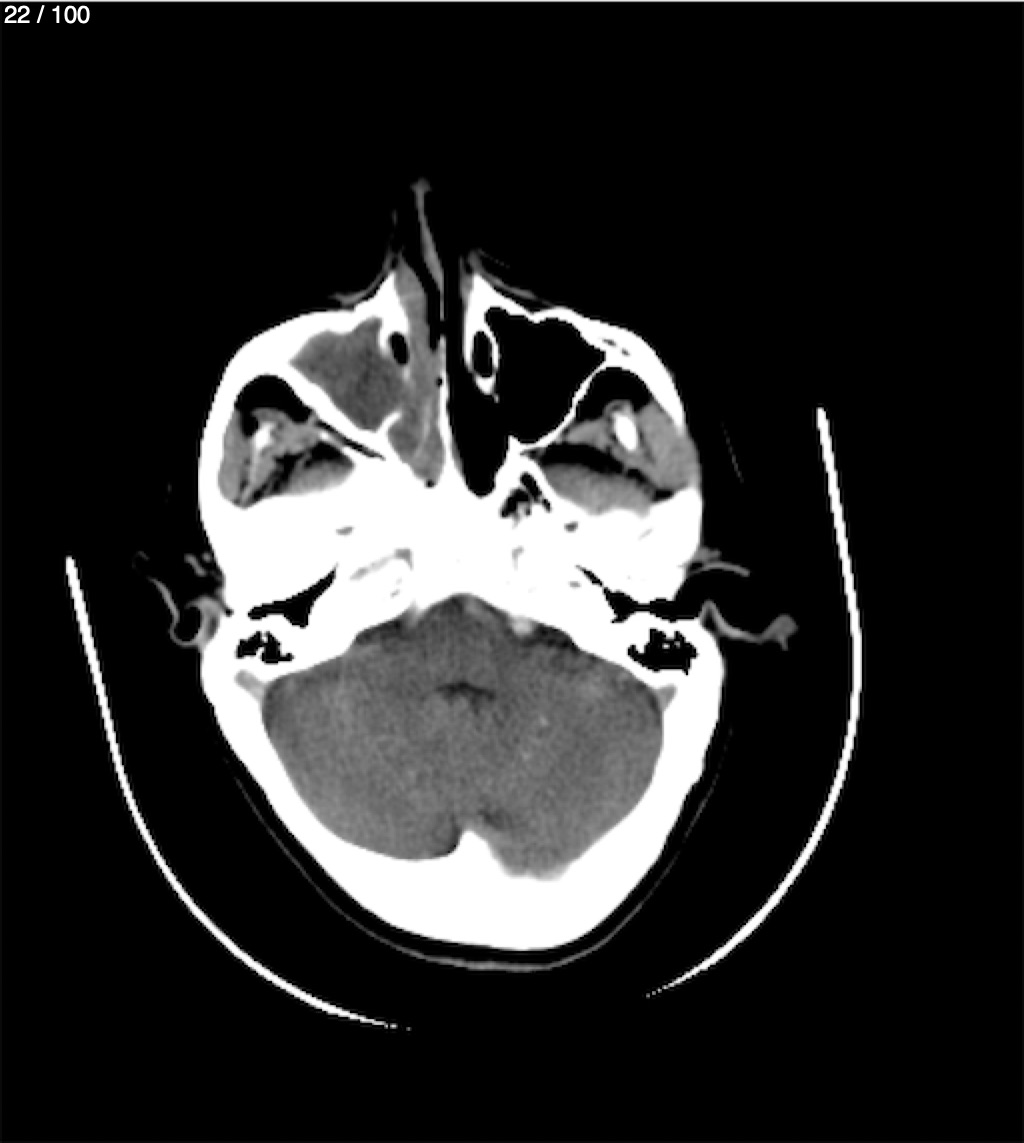

Valentin Perez Gomez 69A - T.C Craneo